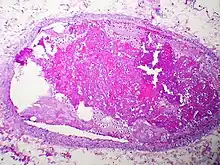

This pulmonary thromboembolism was the result of a thrombus (blood clot) detaching from the wall of a distant blood vessel. It then traveled through circulation until lodging in this pulmonary vessel, becoming a thromboembolism.